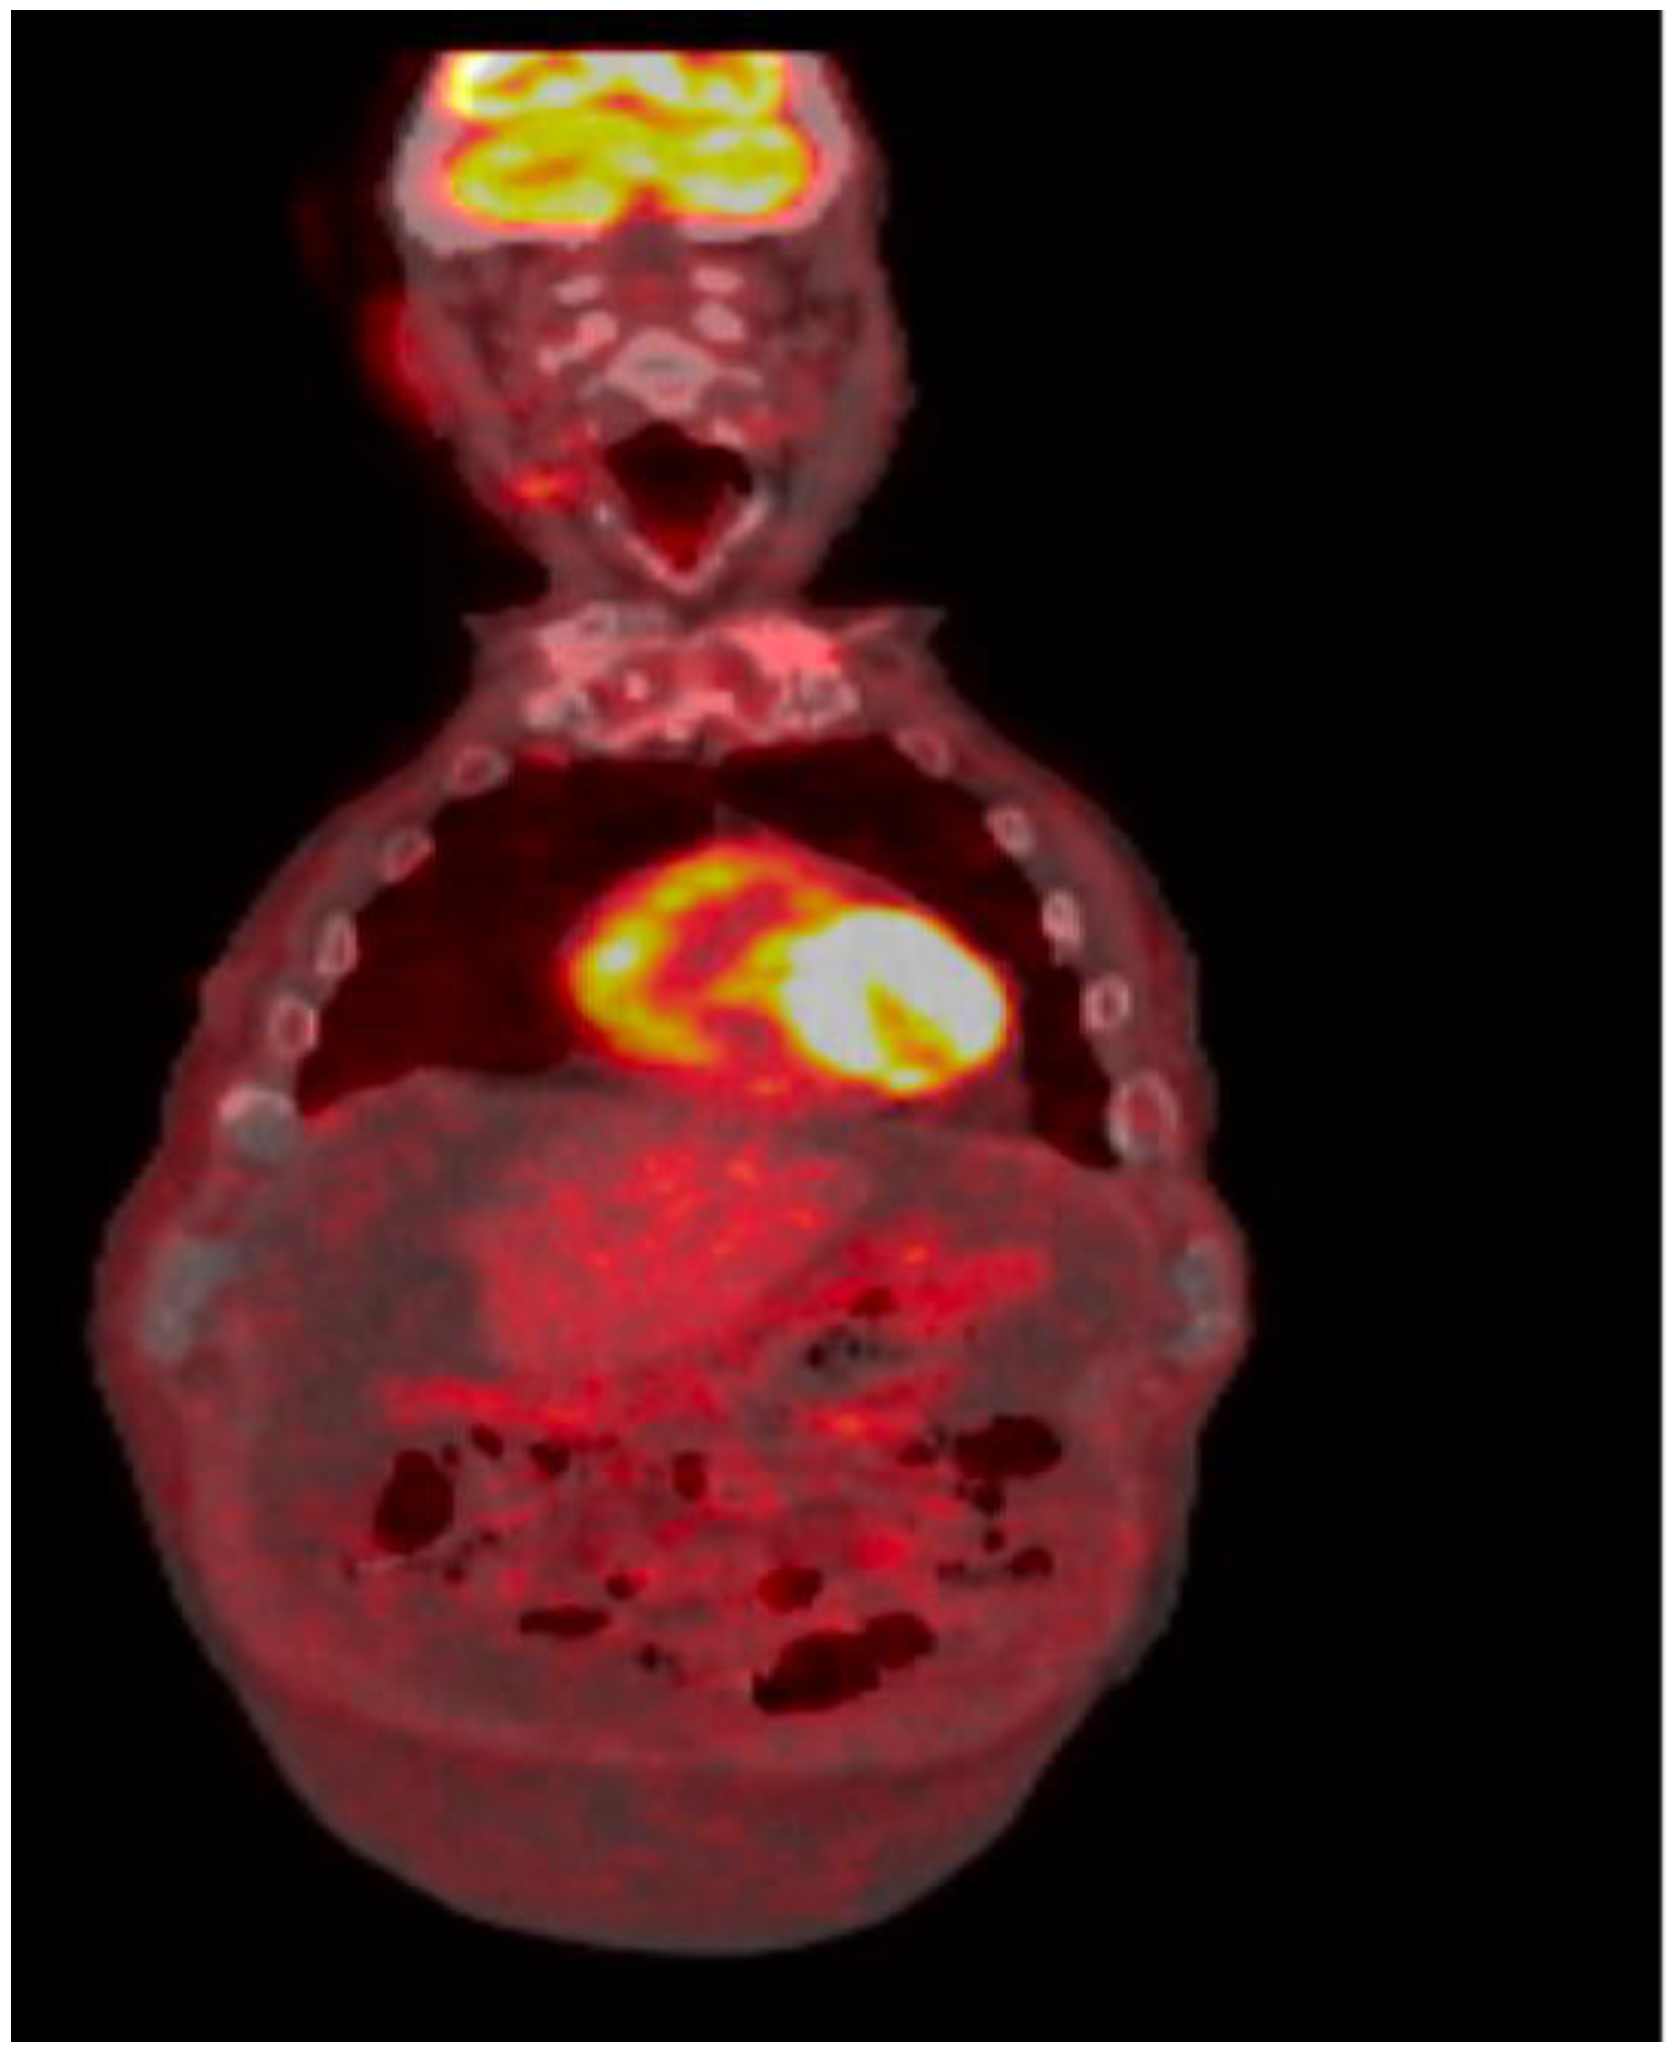

Repeat bone marrow biopsy showed hypercellular marrow with persistent/recurrent involvement by CLL with 35% lymphocytes (Figure 2 and Figure 3). Flow cytometry analysis on bone marrow showed the presence of aberrant clonal B cells (~14% of total events) with the following immunophenotype positive for CD5, CD19, CD20 (dim), CD22, CD23 (subset), CD45, HLA-DR, CD11c (subset), surface Lambda light chain (dim) with a Kappa to Lambda ratio of <1:10 and negative for CD10, CD103, FMC-7, CD38, and surface Kappa light chain. Molecular studies on the bone marrow aspirate did not detect the deletion of 13q, ATM/11q, or TP53 mutation, but was positive for trisomy 12.

Positron emission tomography/computed tomography showed large ascites with omental caking, exhibiting FDG activity with an SUV maximum of 3.1; it also showed mild fluorodeoxyglucose (FDG)-avid right axillary lymph nodes, but no other evidence of the recurrence of CLL (Figure 4).

Figure 2. Bone marrow aspirate with trilineage hematopoiesis and increased lymphocytes.

Figure 4. FDG-PET/CT: Large volume ascites with omental caking, the caking exhibited increased FDG activity with an SUV max of 3.1.